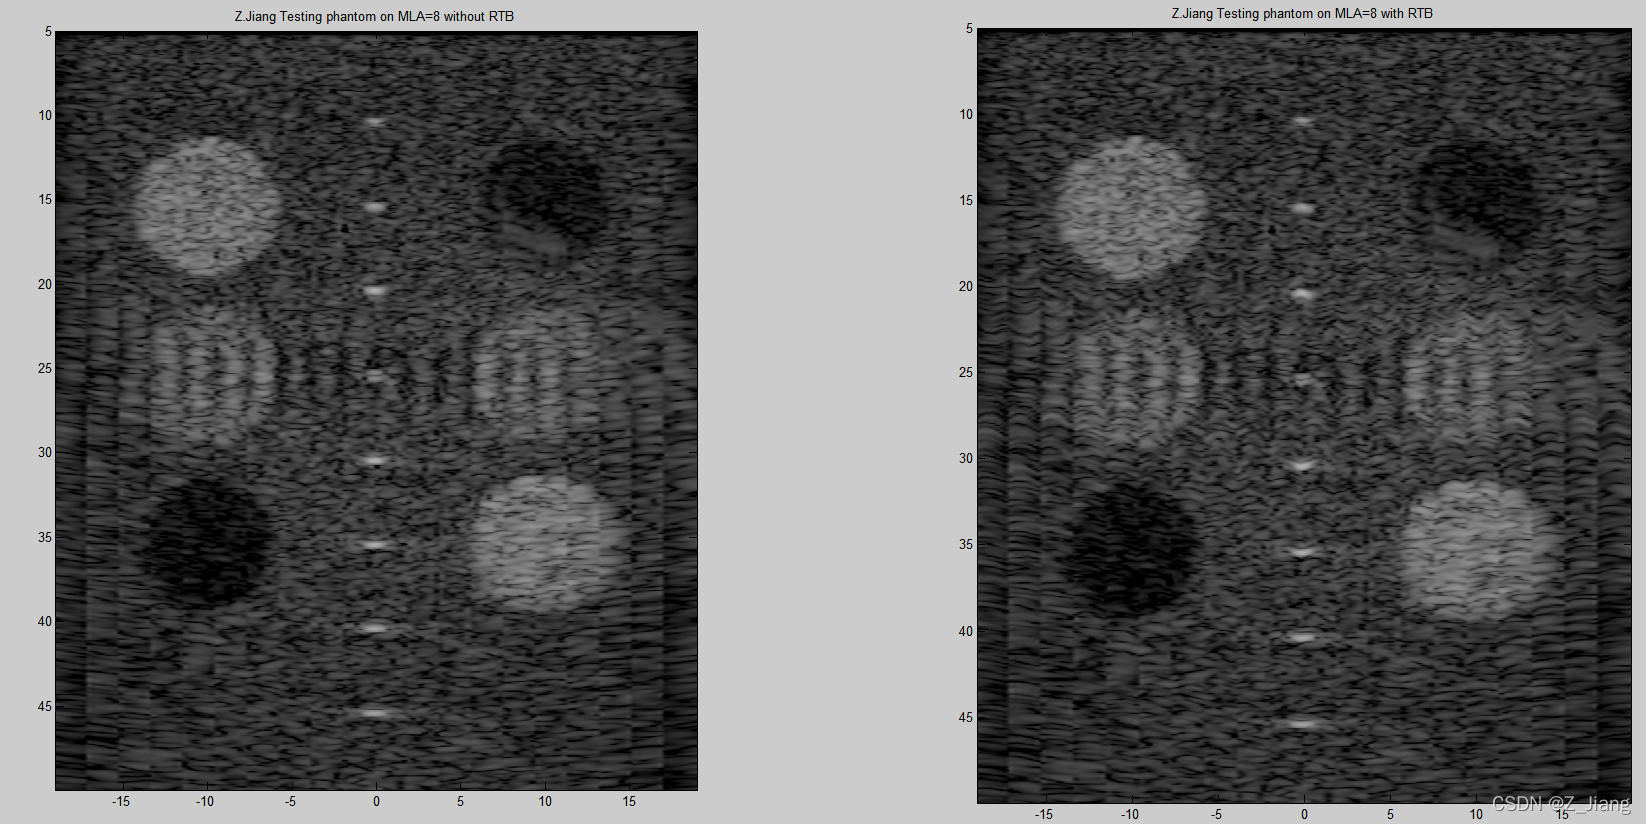

为了对比更明显一些,我以MLA=8的情况进行比较,如下图所示

(PS:下面这个图有问题,但我换电脑时这组数据找不到,这组实验我不打算去改正了。大家正好可以从结果上来找找错。文章后面部分,我会换新数据再做)

MLA=8 comparison between without RTB and with RTB

看上去似乎差别不大,但留意焦点位置,在2.5 cm深度位置的变化。在越远离焦点的位置,波阵面会越来越接近平面波,所以回溯的差别不大,在越接近焦点的地方,差别会越大。这个里面,有一些特殊的处理,我就不展开了。我做成视频,切换着对比,我们就看得更明显一些,如下视频

MLA8 with and without RTB

MLA=8 without RTB and with RTB 切换